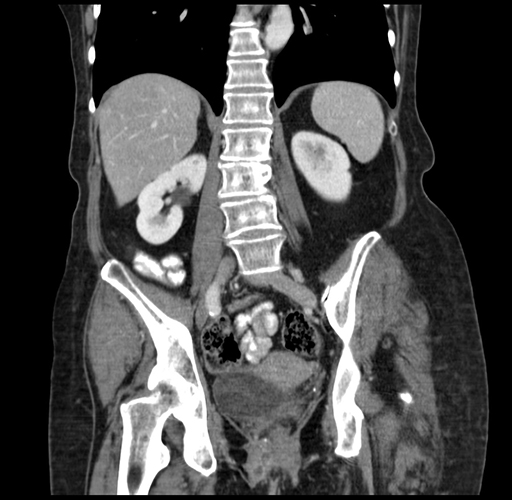

Coronal Venous